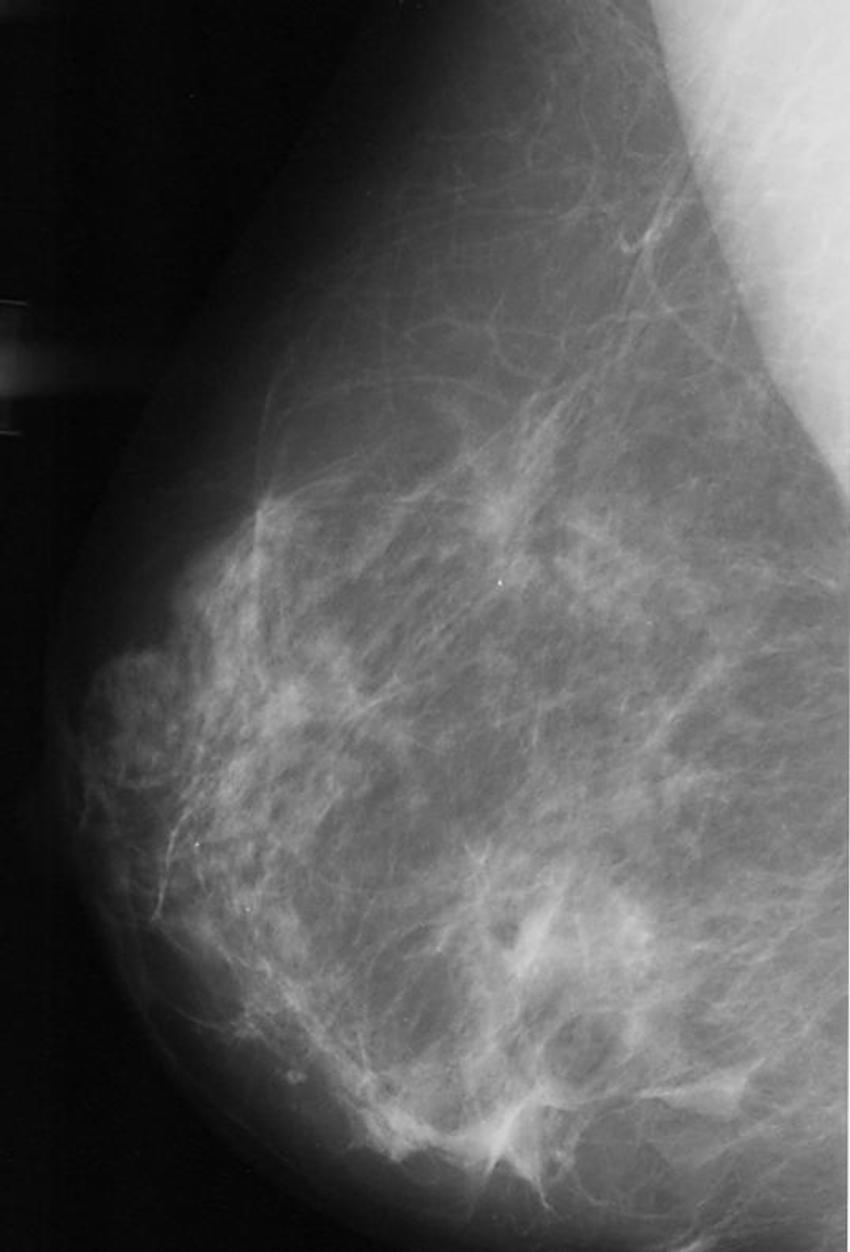

Figure 2. Example of abnormal mammogram.